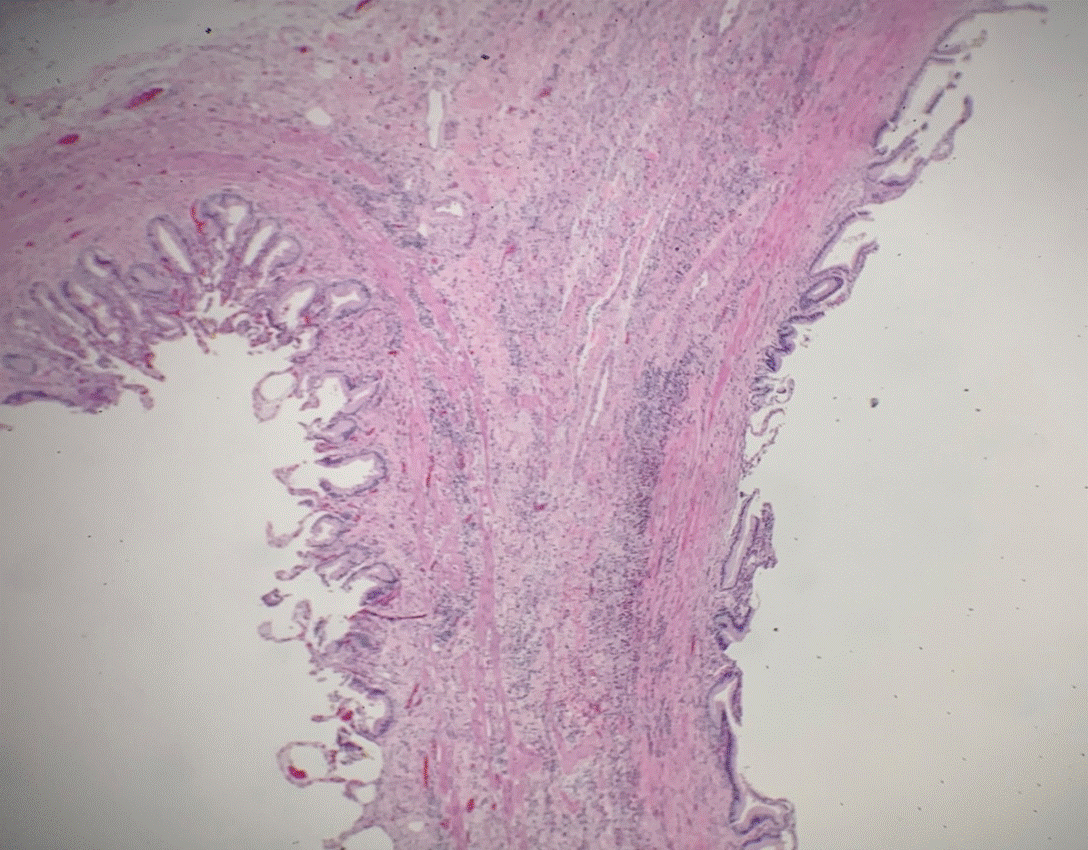

Figure 3. Magnified septal epithelium (10X) showing infiltration of inflammatory cells into the lamina propria and muscularis propria

Figure 4. Magnified fundic epithelium (20X) showing acute inflammation, and two distinct epithelial morphologies